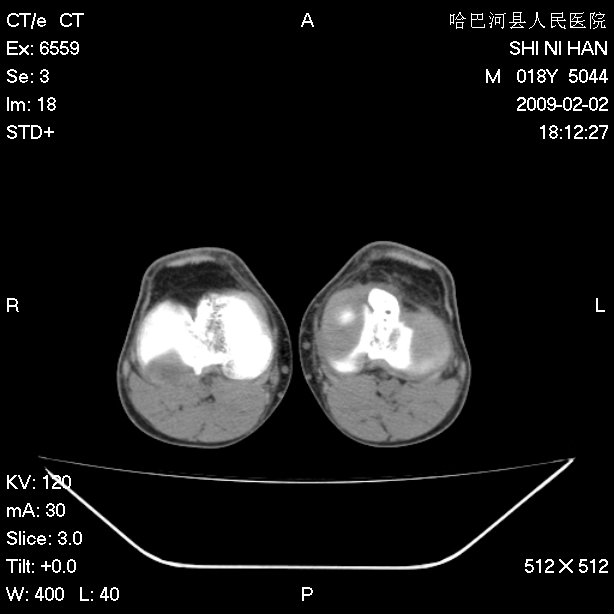

标题: CT17889:外伤后右膝关节反复疼痛3年余 [打印本页]

标题: CT17889:外伤后右膝关节反复疼痛3年余

ct未见明显异常。关节腔未见明显积液,半月板未见明显撕裂。但最好还是mri看看韧带及半月板情况。